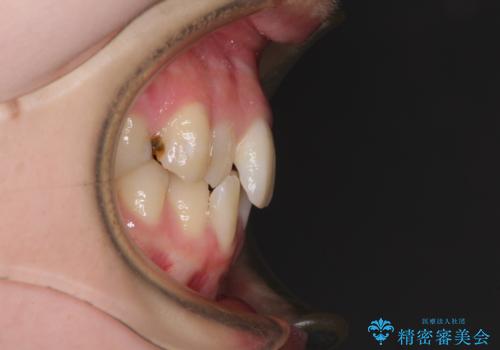

上顎骨の横幅が狭く、上下ともに内側に倒れ込んだ混み合った歯列となっていました。

矯正治療後には、目立つ銀歯と隣接するむし歯をセラミックインレーにて修復治療することとしました。